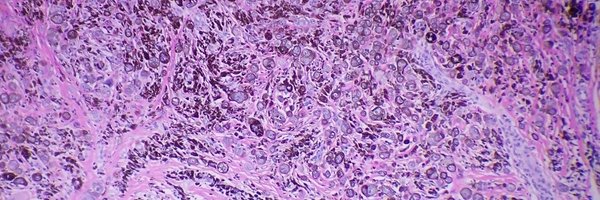

@SGottesmanMD @alegru18 @JCutaneousPath @LinskeyKaty @FungMaxwell @GregHoslerMDPhD @HENRYY_MD @david_terrano @Dermpathl @PIorfino @TristanRutland7 @et565 @maryam_aghighi @JMGardnerMD @caceypeters @pembeoltulu @WMKleinMD @aprimi @DrPatrickRush @sunpungi @MightyDermPath @JRamirezMD @CutisViaLux @RosNazarianMD @AmyHDeekenMD @tonitatirado @VijayPatho @Dr_MikeDeWall @DrGeeONE @dmlarsonpath1 @luishcruzc @KMirza @janavarro_MD @NRiddleMD @Hansalah Our most popular #dermpathJC article in 2021 was "Secondary skin involvement in classic Hodgkin lymphoma" by Dr @alegru18 et al. Incoming talented #dermpath fellow @BloomquistSuzy prepared a post-journal club summary, now live at: https://t.co/Vf7VkSGag5

#hemepath #USCAP22

dermpathjc.wordpress.com

#dermpathJC December 2021 summary Thursday, December 9th, 9pm EST Article discussed: Secondary skin involvement in classic Hodgkin lymphoma: Results of an international collaborative cutaneous…